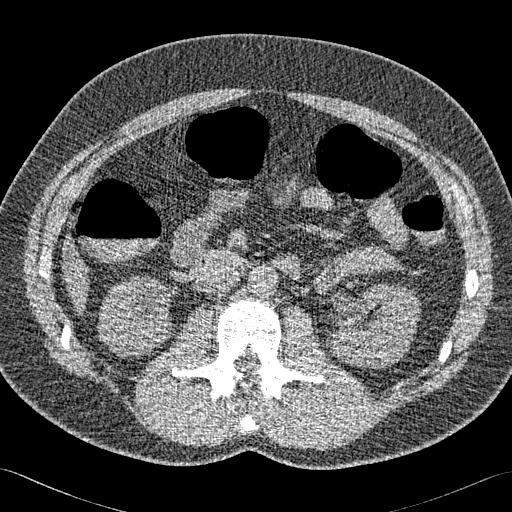

Der Patient muss abführen und bei der Untersuchung den Darm mit Luft aufdehnen, damit sich die Darmwand entfaltet. Dann werden während einer Atemanhaltephase in etwa 20 Sekunden mit einem Röntgen-Computertomografen (CT) circa 800 Bilder transversaler Schichten des Bauchbereichs aufgenommen. Die Helligkeit jedes Bildpunktes gibt an, wie stark an dieser Stelle die Röntgenstrahlung absorbiert wurde.

Das Bild rechts zeigt solch eine transversale Schicht. Die Helligkeitsfluktuation (Bildrauschen) ist typisch für CT-Aufnahmen mit sehr niedriger Strahlungsdosis.